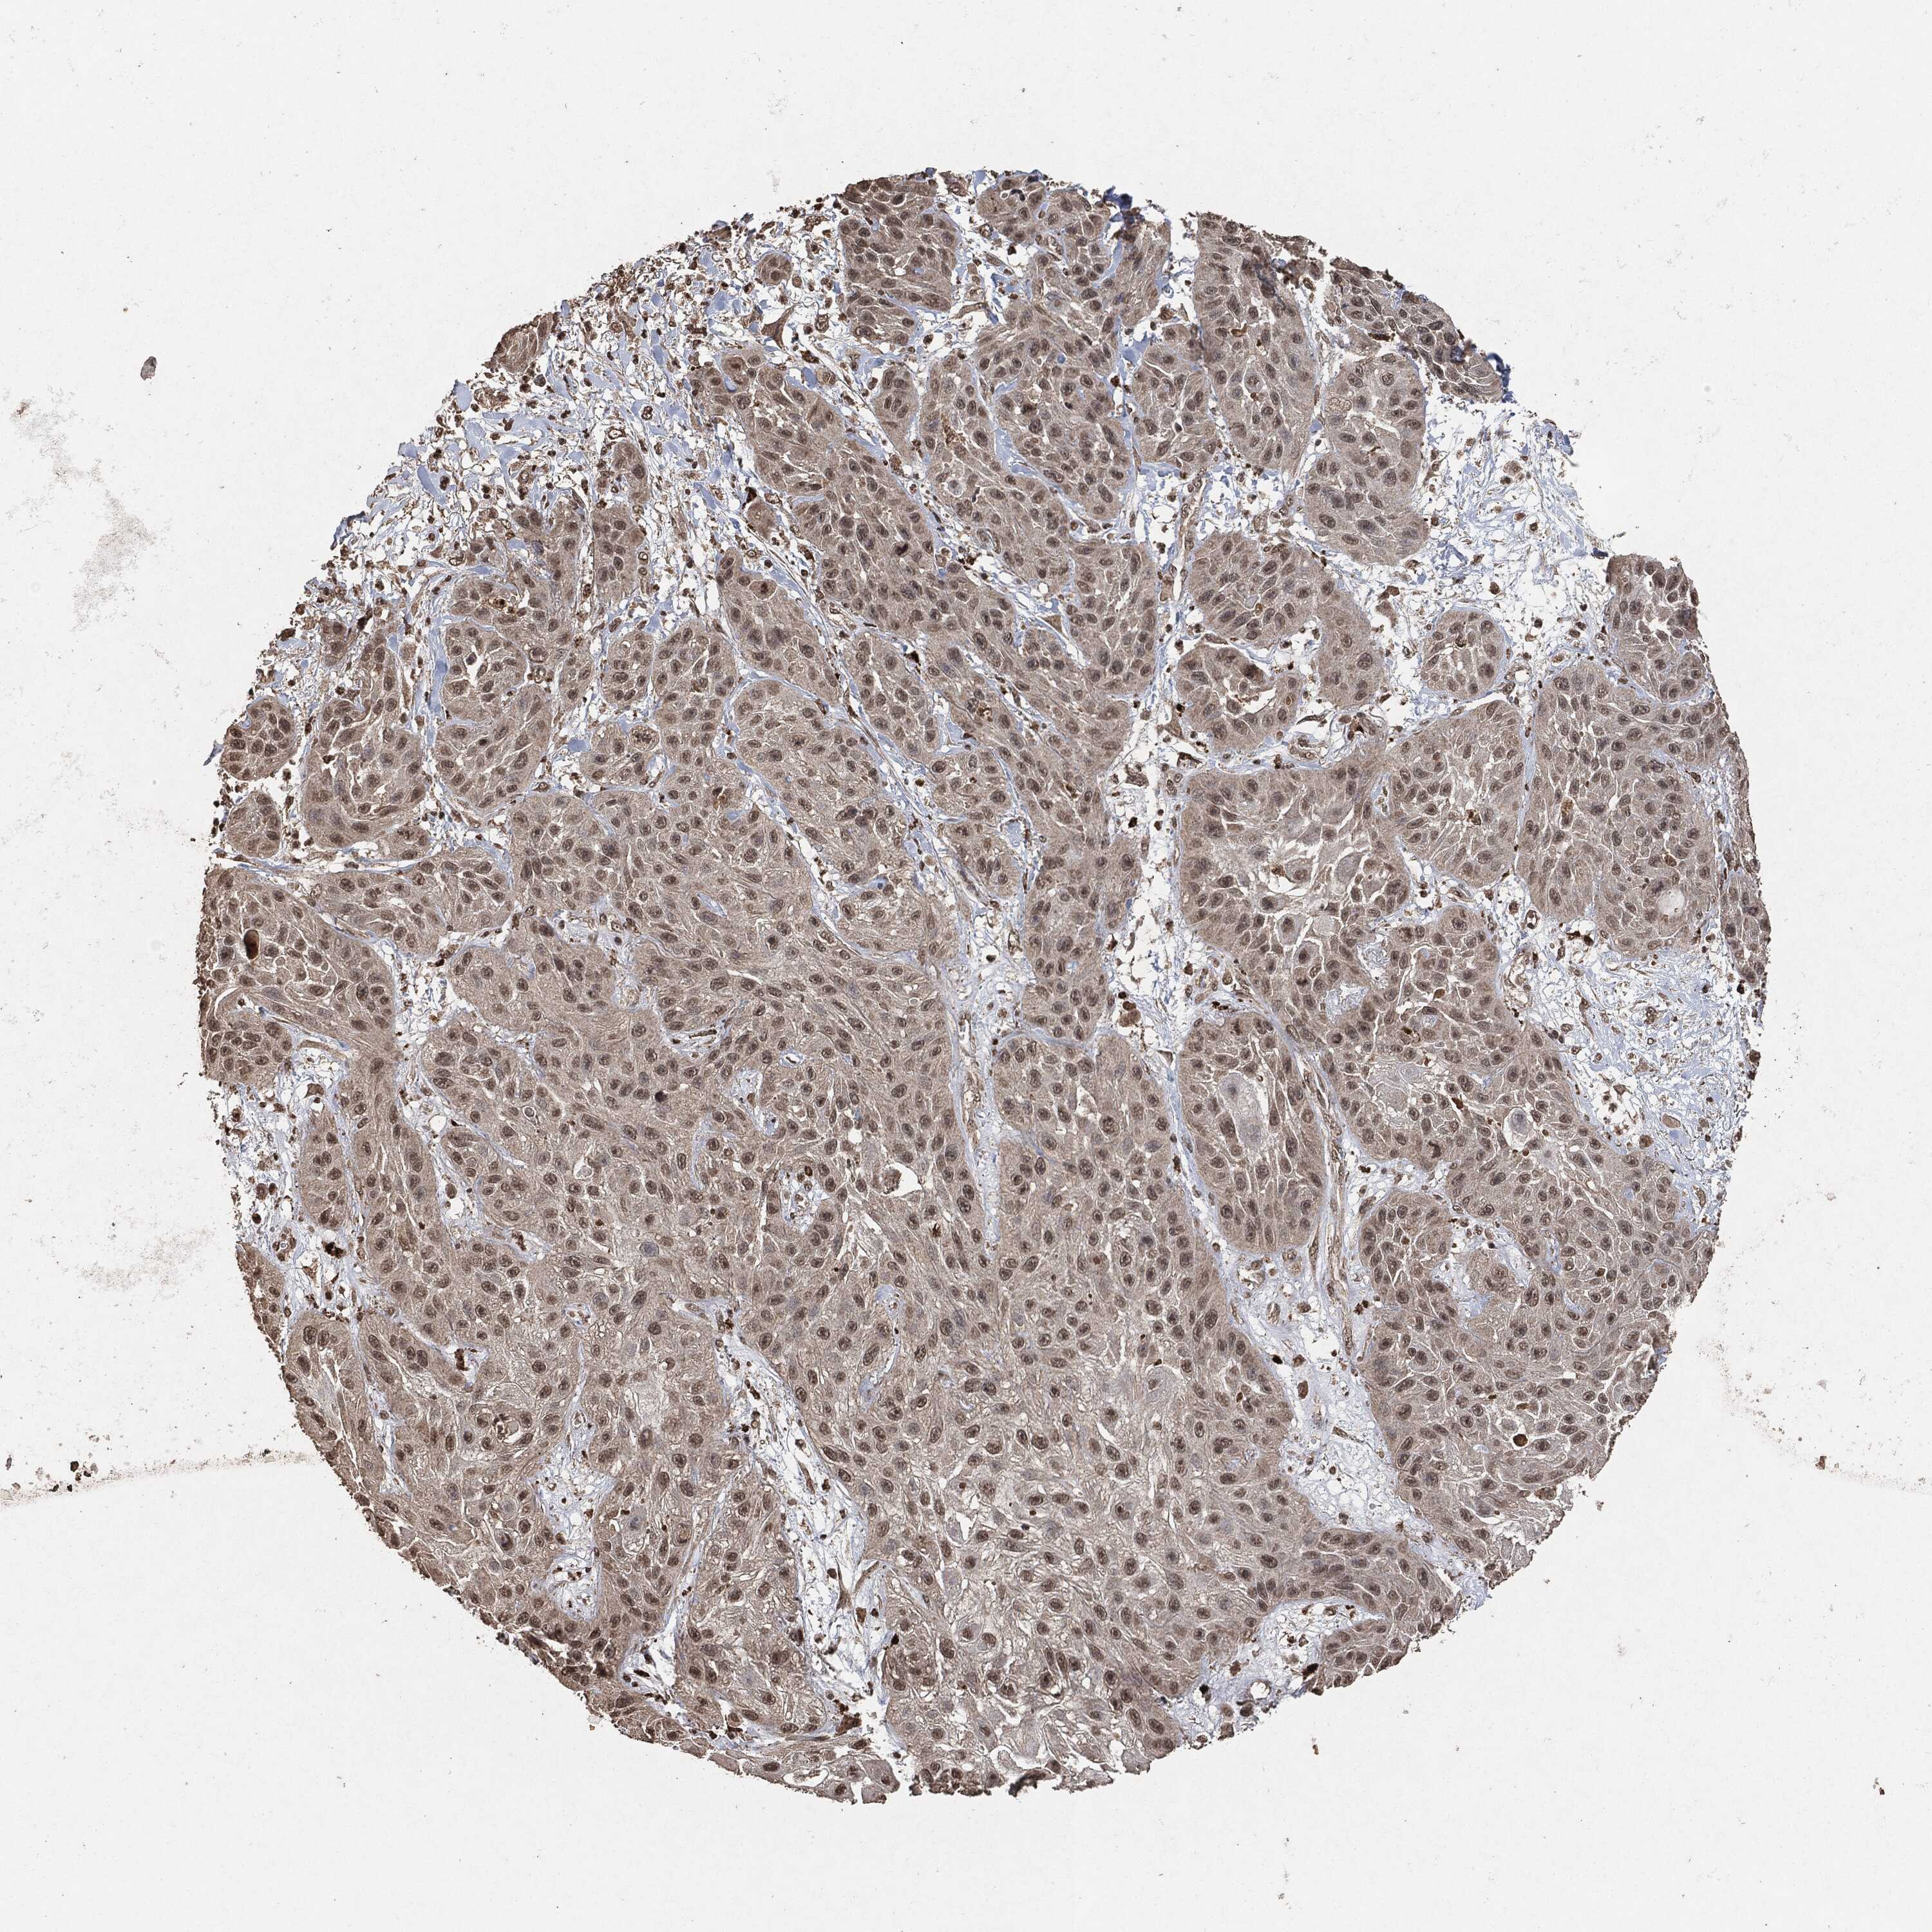

SKIN CANCER - Protein expressioni

A mouse-over function shows sample information and annotation data. Click on an image to view it in a full screen mode. Samples can be filtered based on level of antibody staining by selecting one or several of the following categories: high, medium, low and not detected. The assay and annotation is described here.

Each image is clickable and will lead to virtual microscopy that enables deeper exploration of all samples and also displays staining intensity scores, fraction scores and subcellular localization as well as patient and tissue information for each sample.

HPA001200

Staining

High

Medium

Low

Not detected

Squamous cell carcinoma, NOS

Basal cell carcinoma

Squamous cell carcinoma in situ, NOS

Squamous cell carcinoma, metastatic, NOS